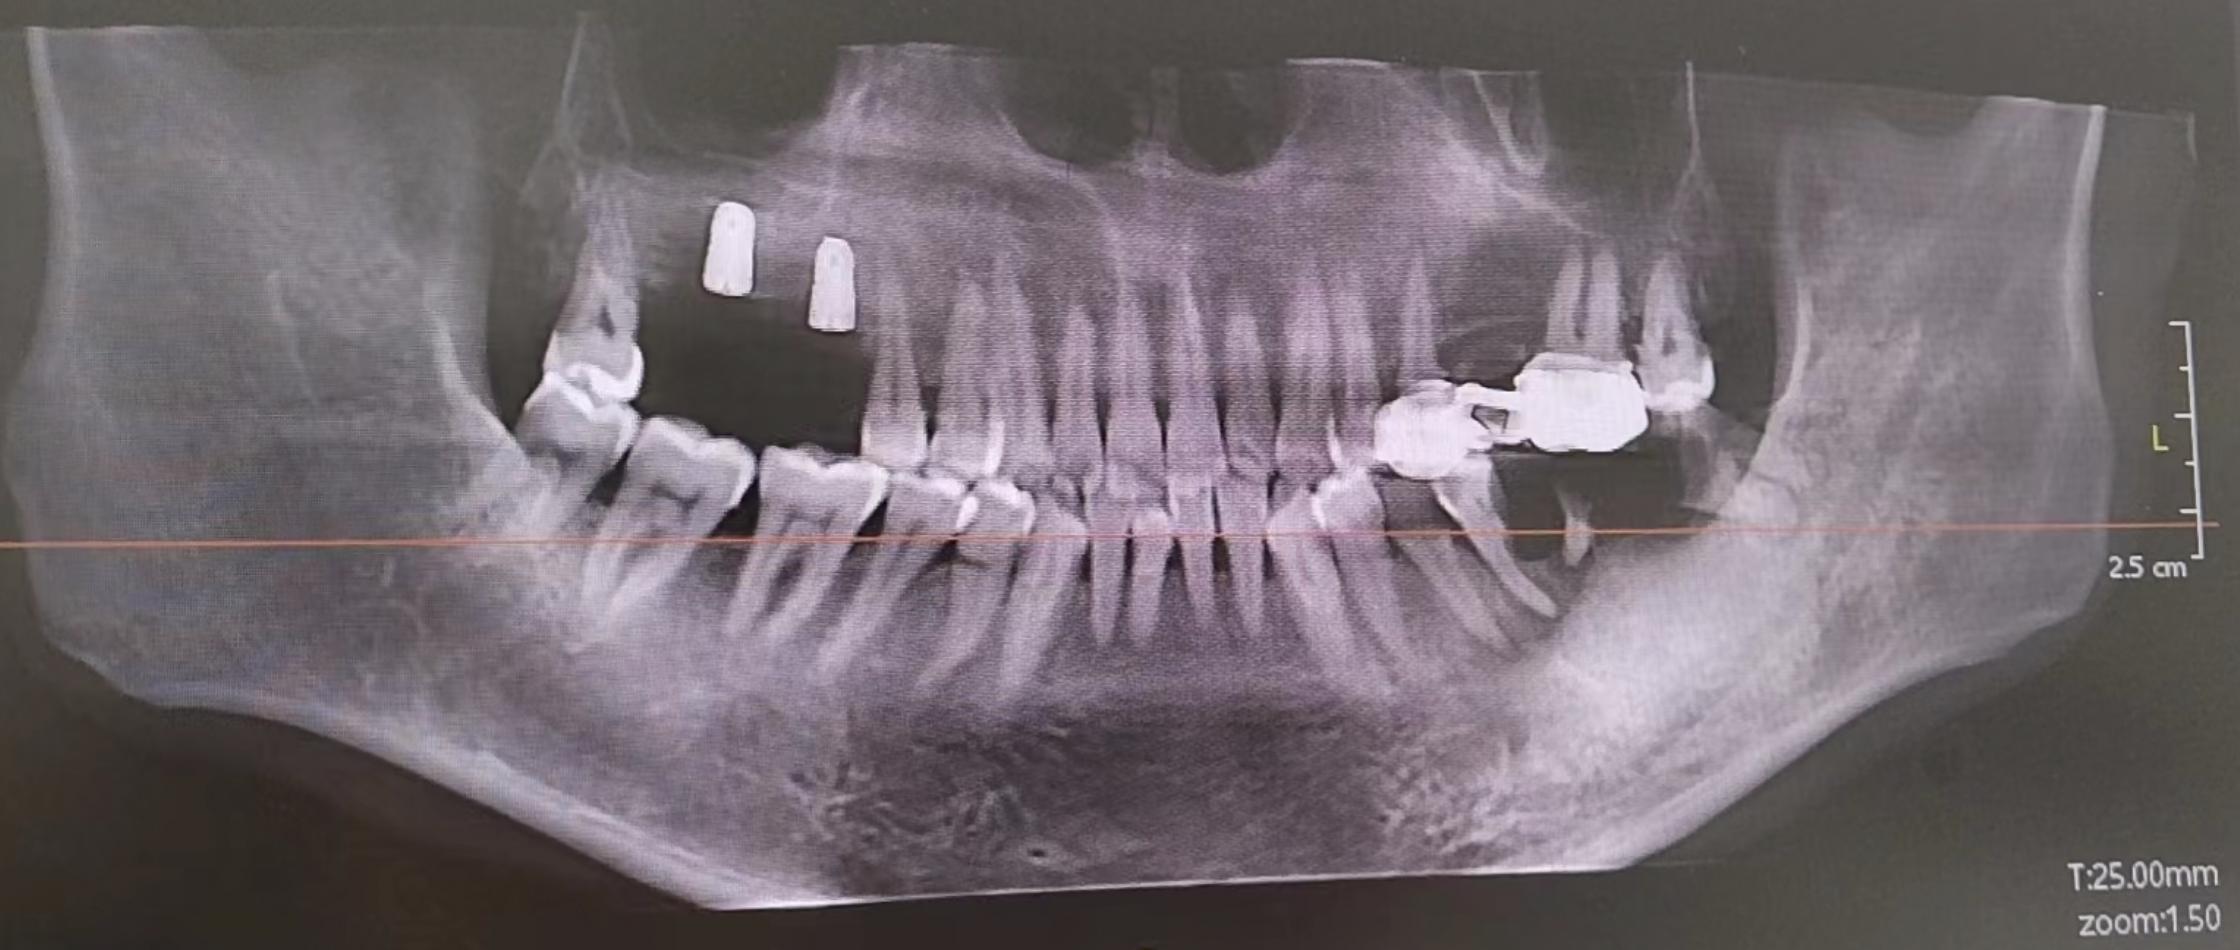

前段时间他说牙齿坏了,已经严重影响到日常一日三餐的程度,所以我赶紧让他过来看看牙齿。正好我家附近就有牙科诊所,拍了X光发现两侧的磨牙都有不同程度的缺失,共缺失5颗,还有3颗需要重新装牙冠。初步方案是4颗种植牙+4个牙冠(有3颗连续缺失可采用种2颗搭一个牙冠的方案)。这里科普一下,种植牙一般可拆分为3个部件:种植体、基台跟牙冠。一般需要把剩余的牙根拔除,等3个月完全愈合后进行手术把种植体打入颌骨(约30分钟,7~10天后拆线),再等3个月等待种植体跟颌骨结合牢固,就可以进行基台跟牙冠的安装。

等3个月之后带着我爸就去了。这家的规模比之前的小诊所大了很多,而且服务也比较好。重新拍了片子,他们给的方案是种5颗+3个牙冠,用的还是奥齿泰和国产全瓷牙冠的组合(美国皓圣报价5200,有点小贵)。一阵软磨硬泡之后最后的价格是4000*5+900*3,一共22700。

已经种了2颗植体的X光